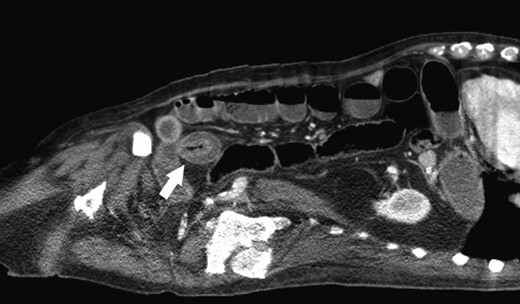

An 86-year-old male previously treated for hypertension presented to the emergency department with two days of sudden abdominal pain and nausea which resolved temporarily after self-induced emesis. Patient was examined and investigated thoroughly. Temperature was 36.3 C, blood pressure was 138/81, and pulse was 78. Physical examination revealed a tender, firm and distended abdomen with hyperactive sounds. Laboratory analysis revealed hemoglobin at 10.3 g/dL, leukocytes 3.1 K/cmm, urea nitrogen 19 mg/dl, creatinine 0.6 mg/dl, sodium 137 mmol/l, potassium 3.6 mmol/l, chloride 104 mmol/l, bicarbonate 24 mmol/l, calcium 8.6 mg/dl, total protein 6.3 g/dl, albumin 3.1 g/dl, total bilirubin 0.7 mg/dl, alkaline phosphatase 98 U/l, SGOT 20 U/l, SGPT 27 U/l. Laboratory values were consistent with patient’s previous clinic visits. Computed tomography (CT) of the abdomen revealed a fluid-filled, significantly dilated stomach as well as multiple dilated loops of small bowel with air-fluid levels consistent with mechanical small bowel obstruction caused by intussusception of small bowel (Fig. 1). After initial fluid resuscitation and antibiotic administration, consent was obtained for emergent exploratory laparotomy. The exploratory laparotomy revealed a 3.0 × 2.5 cm intraluminal calculus in the ileum responsible for the small bowel obstruction, without evidence of intussusception (Fig. 2). The obstructing enterolith was ‘milked’ proximally until it reached, and subsequently ‘fell into,’ an isolated 6.0 × 3.0 cm jejunal diverticulum which had not been previously noted on CT imaging. The enterolith was removed along with the segment of the jejunum containing the isolated diverticulum, which was the source of the enterolith (Fig. 3). On histologic examination, the mucosa of the extracted diverticulum was found to be granular and erythematous; the remaining small bowel had marked mucosal ulceration and near-transmural inflammation with granulation tissue. Hospital course was complicated by decreased urine output that resolved after fluid resuscitation. On the fourth postoperative day, nasogastric tube was discontinued, diet was advanced and tolerated, and the patient was discharged. Review of the patient’s CT scan of the abdomen revealed the isolated jejunal diverticulum that was consistent with the excised diverticulum (Fig. 4).

Enterolith-induced small bowel obstruction resembling intussusception (white arrow).